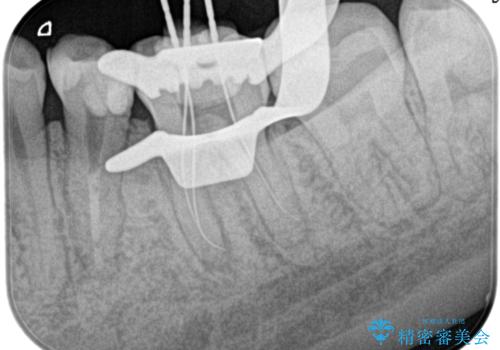

精密根管治療。大臼歯イニシャルケース

- 奥歯がズキズキ痛いことを主訴に来院されました。

検査の結果、診断を症候性不可逆性歯髄炎、症候性根尖性歯周炎とし抜髄を行っております。

根管充填はCWCTにて行なっております。

根管形成はマルテンサイト相を有するNi-Tiロータリーファイル(NEX MS)使用。